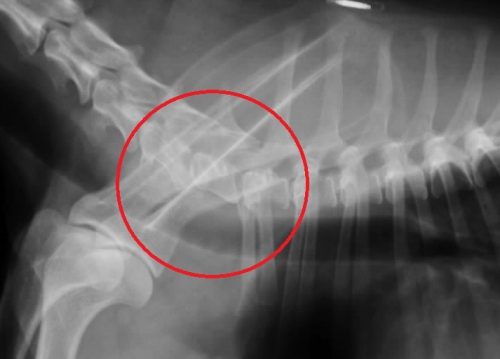

下の写真は日常的に常に頸部の痛みを訴えており、前足の歩行にも問題を生じている患者さんの重度の頸椎~胸椎の変形性脊椎症のレントゲン写真です。

左下の写真、赤丸の中に病変があり、各々の椎骨は両端が大きく変形しております。右下写真は同じ部位の正常なレントゲン写真です。左右の赤丸内の骨の変形が大きいのがお分かりになるかと思います。